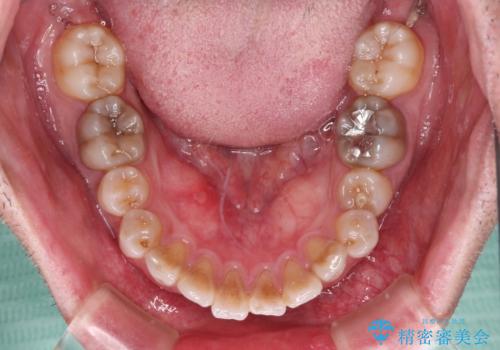

- 飛び出した前歯を気にして来院された患者様です。

口元を引っ込めるために上下左右の第一小臼歯4本を抜歯することとしました。

速やかに治療を進めたいとのことで、表側のワイヤー装置で矯正治療を行うこととしました。